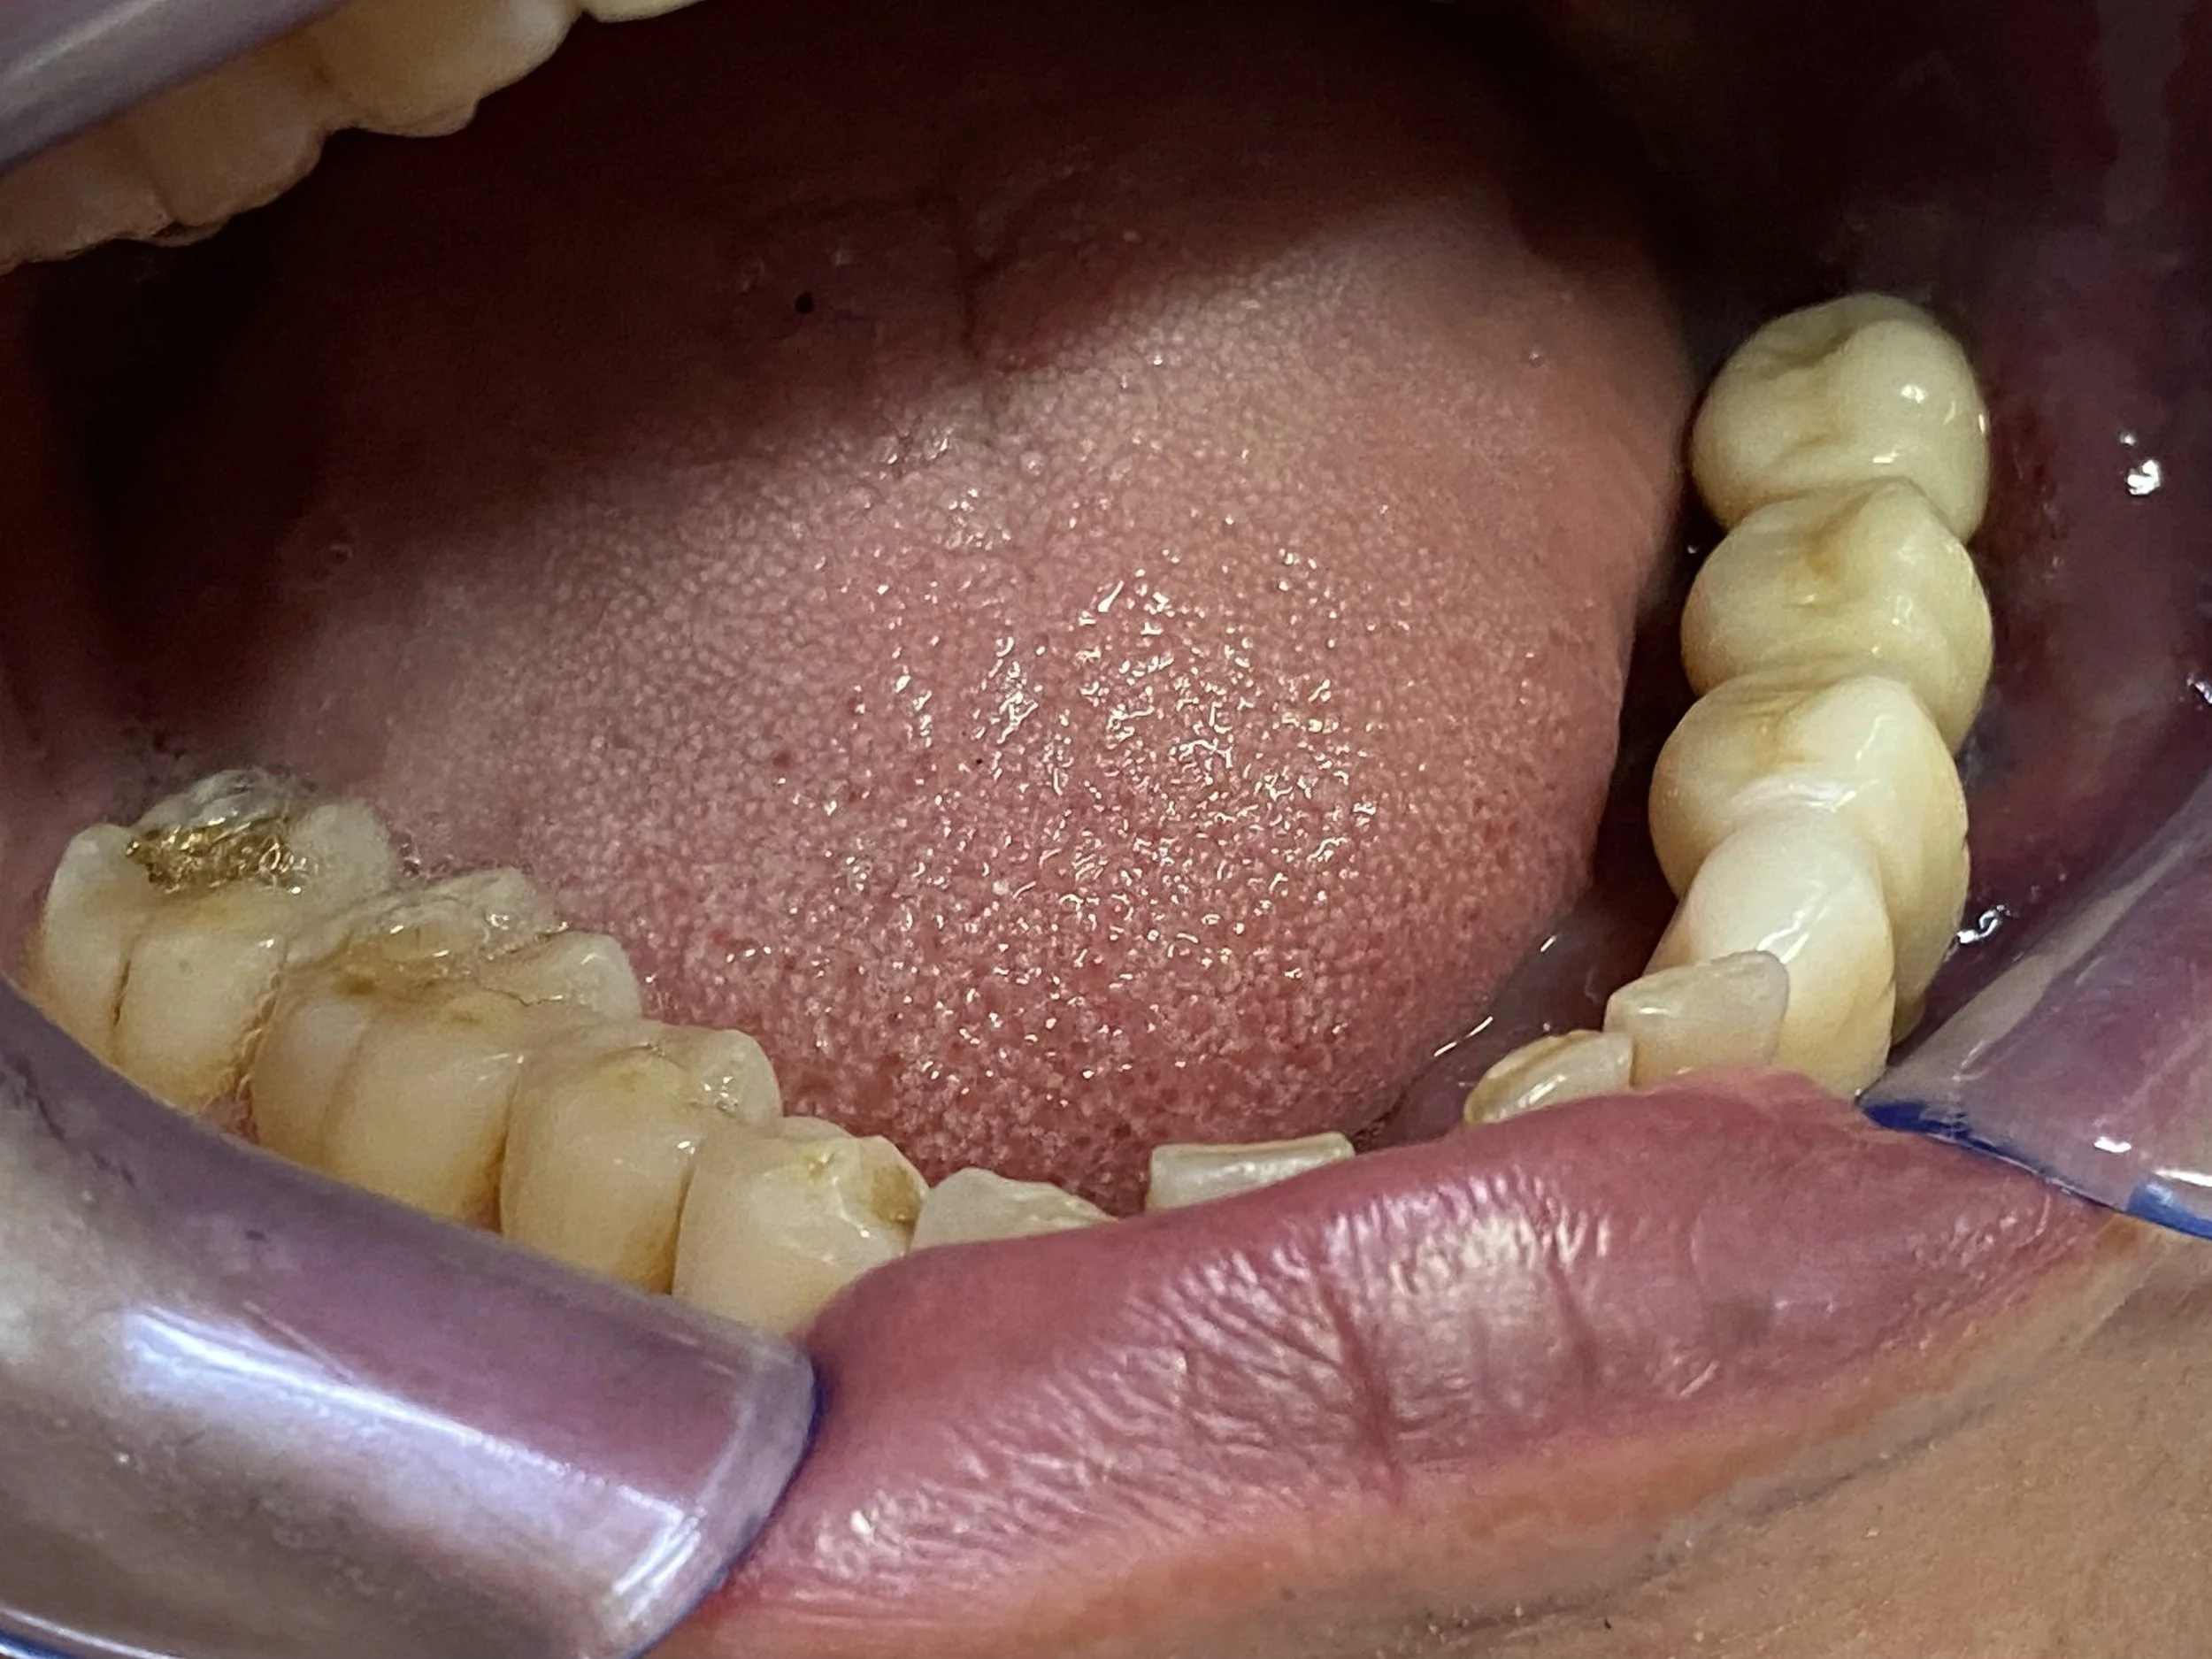

This 50 year old gentleman suffered severe dental wear, and heavily filled and stained teeth.

-

He endured a fractured lower jaw from a car accident resulting in the loss of the lower left canine with a residual space and a metal splint to fixate the broken jaw as is illustrated

Subsequently, the upper left front tooth fractured and was removed and I surgically placed a Branemark implant fixture/implant crown